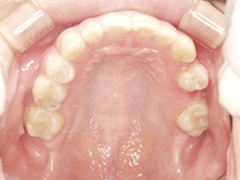

写真(1)口内写真

歯周病の進行により、上顎の歯は全て抜歯しなくてはならない状態